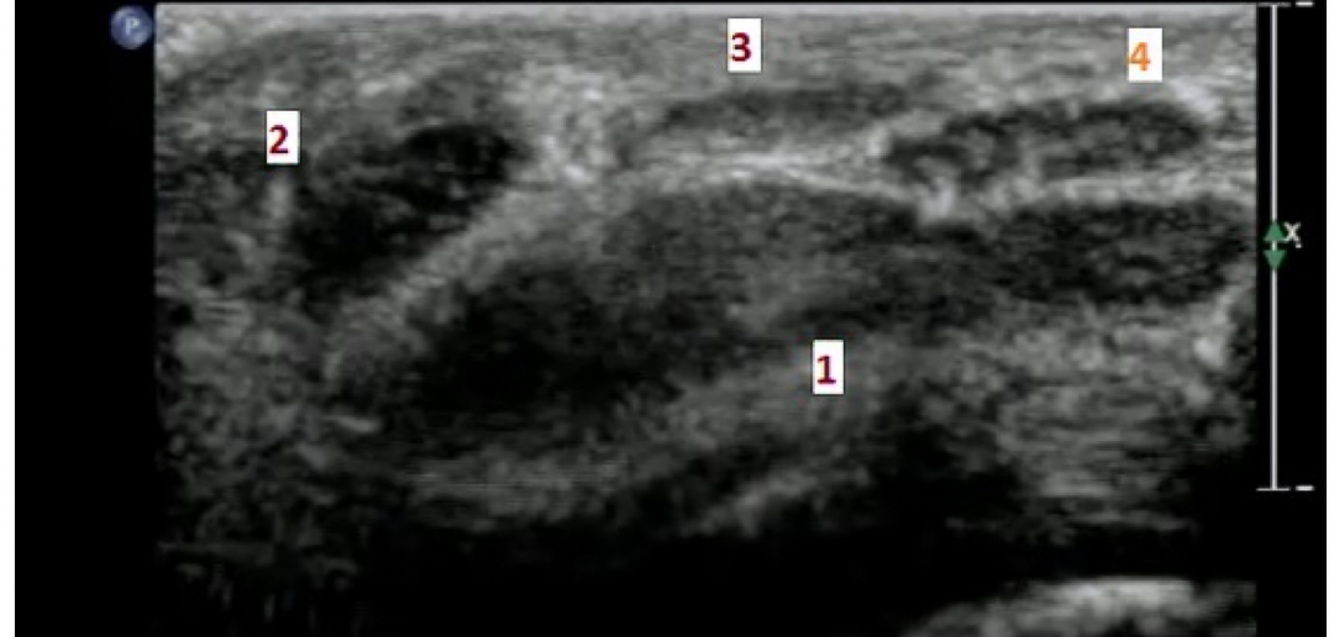

Acoustic enhancement also called posterior enhancement or enhanced through transmission, refers to the increased echoes deep to structures that transmit sound exceptionally well. This is characteristic of fluid-filled structures such as cysts, the urinary bladder, and the gallbladder. The fluid attenuates the sound less than the surrounding tissue. The time gain compensation (TGC) overcompensates through the fluid-filled structure causing deeper tissues to be brighter. Simply it is seen as increased echogenicity (whiteness) posterior to the cystic area.